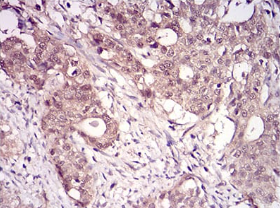

IHC    1/100 - 1/500